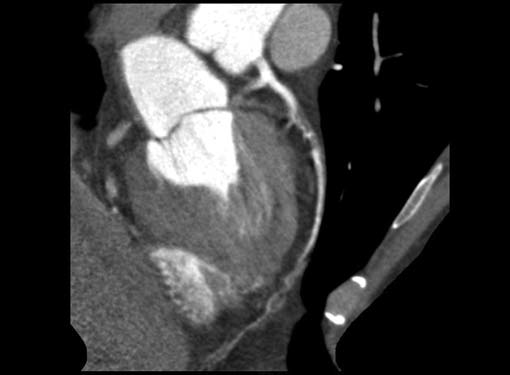

CT is the preferred tool of investigation of coronary bypass grafts (Fig. 9). Reversed saphenous vein grafts (SVGs) are optimally studied consistently. Anastomotic sites are studied effectively. However, distal anastomosis of venous graft to obtuse marginal branch (OM) is relatively difficult to evaluate because of diminishing caliber of native vessel. Arterial grafts pose a small challenge due to artifacts of associated surgical clips (Figs 10A and B). Ostium and proximal part of graft are assessed well. However, distal anastomotic site may be difficult to assess on occasions. RIMA graft, posterior descending artery (PDA) graft, gastroepiploic artery graft can also be studied. Stenosed venous grafts

can be stented and the same can be evaluated by CT (Fig. 11). Like native RCA, RCA grafts (Figs 12A and B) are more susceptible to motion artifacts when compared to LAD and OM grafts. Catheter angiogram can be used to answer specific queries after CT angiogram.